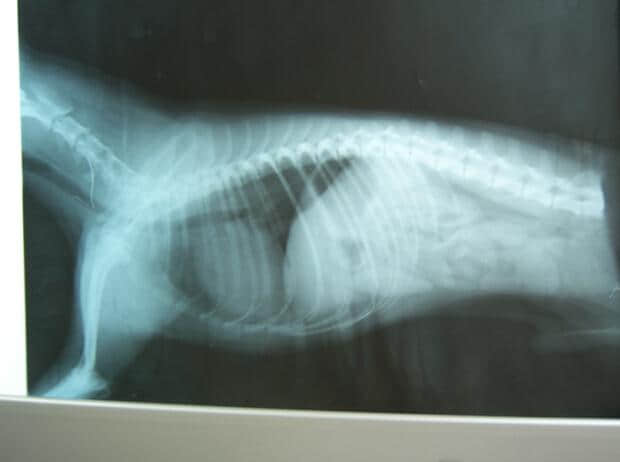

2.2 X光检查:见下图

侧位:显示脾区肿大

由于致敏的红细胞在脾脏内淤积和大量崩解,导致脾脏肿大。